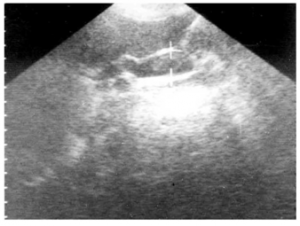

בדיקה חשובה לאבחון אבנים בדרכי מרה היא האולטרה-סאונד האנדוסקופי (EUS) שאמינותה גבוהה מאוד (תצלום 32.8).